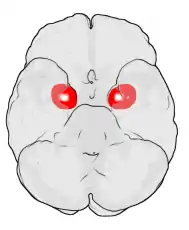

![]() Subdivisions of the amygdala | |

The regions described as amygdala nuclei encompass several structures of the cerebrum with distinct connectional and functional characteristics in humans and other animals.[5] Among these nuclei are the basolateral complex, the cortical nucleus, the medial nucleus, the central nucleus, and the intercalated cell clusters. The basolateral complex can be further subdivided into the lateral, the basal, and the accessory basal nuclei.[3][6][7]